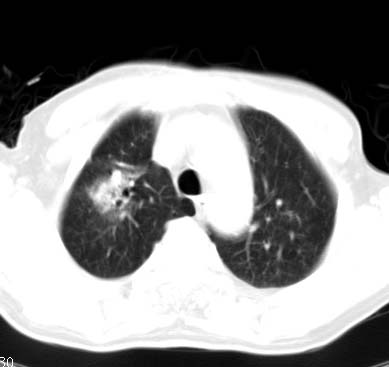

标题: CT14027:男性病人 71岁 咳嗽咳痰数周. [打印本页]

标题: CT14027:男性病人 71岁 咳嗽咳痰数周.

男性病人 71岁 咳嗽咳痰数周.诊断结核应该有保障吧!

右上肺结核,请结合痰检除外活动期;右上叶支气管官腔狭窄建议支气管镜或抗僗后随诊除外堵塞性改变。

高度怀疑肺癌,强烈要求纤支镜检查。

支持双上肺继发性肺结核。